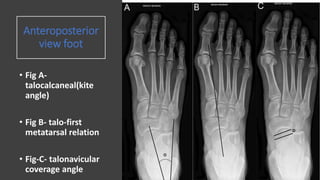

Anteroposterior

view foot

• Fig A-

talocalcaneal(kite

angle)

• Fig B- talo-first

metatarsal relation

• Fig-C- talonavicular

coverage angle